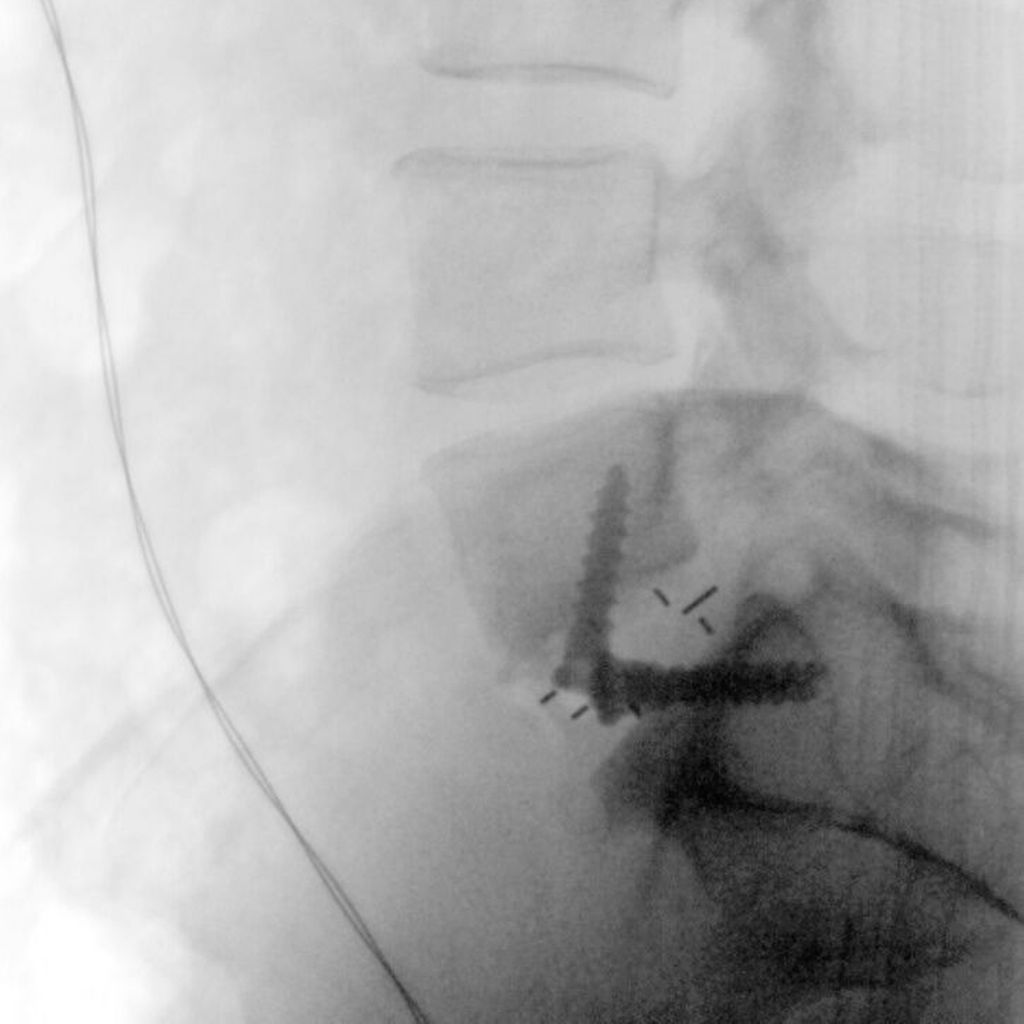

Nach einer medianen Hautinzision bzw. Pfannenstielinzision erfolgt meist ein linksseitiger retroperitonealer Zugang in Rückenlage. Bei einer ventralen multisegmentalen Fusion empfiehlt sich eine paramediane Längsinzision. Nach Darstellen und Inzision der vorderen Rektusscheide sowie Mobilisierung des Muskels wird das Peritoneum stumpf gelöst und mitsamt dem Ureter nach medial präpariert. Danach wird der Bandscheibenraum L5/S1 unterhalb der Gefäßbifurkation dargestellt. Ein Zugang zu den Bandscheibenräumen L4/L5 und darüber erfolgt am medialen Rand des Musculus psoas. Das hintere Blatt der Rektusscheide muss eventuell inzidiert werden. Die Arterie und Vena iliaca communis sowie kranial davon die Vena cava inferior und Aorta abdominalis werden dabei vorsichtig stumpf von lateral nach medial mobilisiert. Bei L4/L5 ist im Besonderen auf eine mögliche Vena iliolumbalis oder Vena lumbalis ascendens zu achten, welche entsprechend ligiert werden sollten. Nach erfolgter Darstellung der vorderen Säule und Einstellen des Situs mit einem in den meisten Fällen selbsthaltenden Retraktorsystem erfolgen das Durchtrennen des vorderen Längsbands und das Ausräumen des Bandscheibenfachs (Abb.1). Anschließend wird der Probecage unter Röntgenkontrolle eingebracht und schließlich das definitive Implantat (Abb. 2). Je nach Implantat kann der Cage mit einem integrierten Schraubensystem in den angrenzenden Wirbelkörpern fixiert werden (Abb. 3, 4).